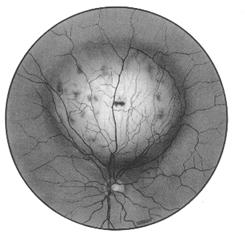

leziuni coroidiene si retiniene: buton coroidian unic sau noduli grupati cu aspect de placard alb-galbui, usor proeminent, cu contur imprecis, care in evolutie lasa leziuni cu aspect de plaje de atrofie corioretiniana alba, cu margini pigmentate. Leziunile pot fi in focar unic, multifocale, sau difuze (Fig. 12.3/4 -vezi plansa).

Fig. 12.3 - Corioretinita cicatriciala Fig. 12.4 - Corioretinita in focare multiple